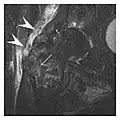

- a

- b

- c

Figure 1: A 56-year-old woman presenting with left knee pain after a fall. (a) Initial anteroposterior radiograph was considered normal, however, subtle cortical disruption of the anterior rim of the medial tibial plateau, medial to the tibial spine, is noted (arrow). (b) Coronal T1-weighted MRI confirms the cortical disruption (arrow) and shows extensive fracture through the proximal tibia. (c) Coronal proton density-weighted image with fat saturation shows extensive edema in the subchondral bone. Note also hypersignal adjacent to the medial collateral ligament corresponding to a grade I sprain (arrowheads).[1]